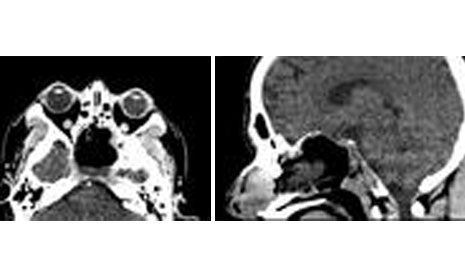

19. Cervical listhesis -traumatic